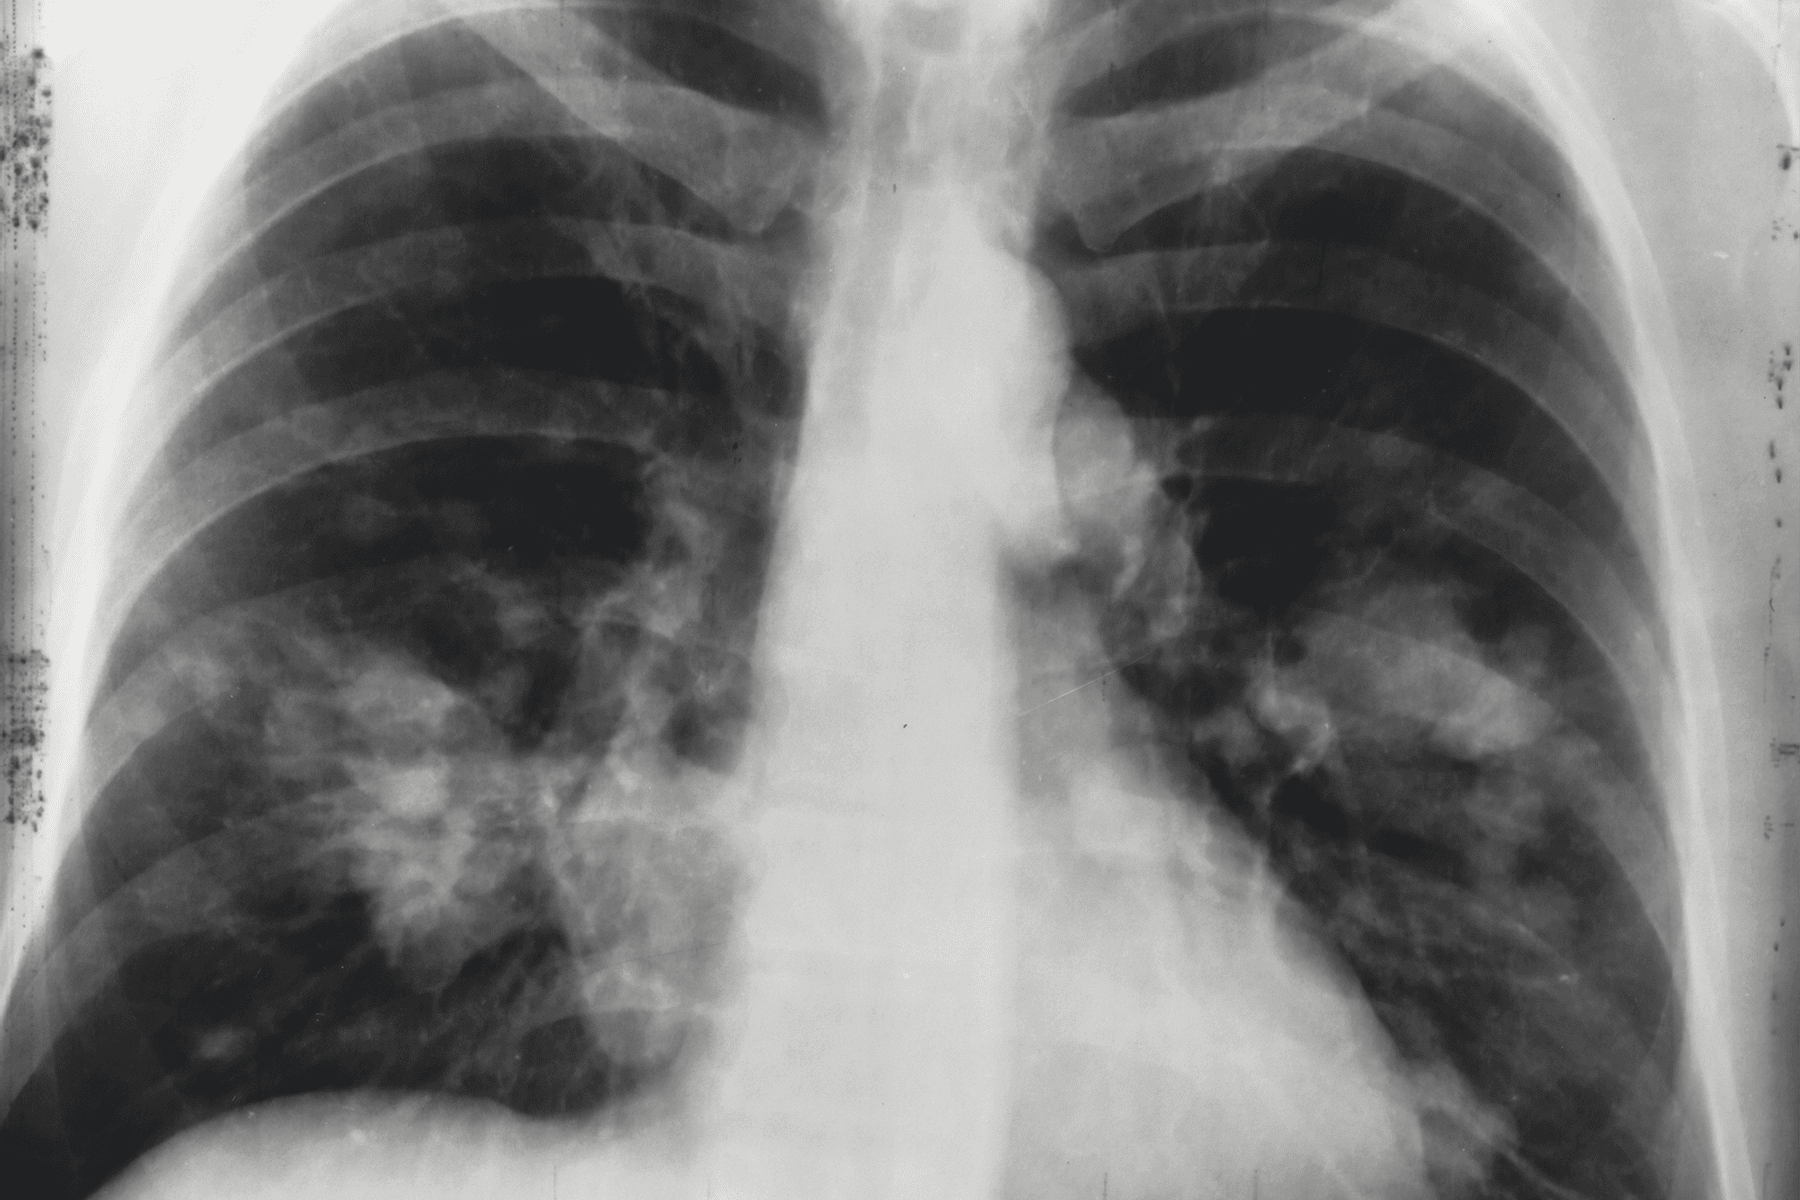

Pulmonary Embolisms

Failure to diagnose pulmonary embolisms — potentially fatal blood clots in the lungs — can lead to severe complications or death; accordingly, this may result in medical malpractice lawsuits.

Failure to Diagnose Cancer

A doctor may fail to diagnose cancer due to various reasons that could constitute medical malpractice.

These may include inadequate training or knowledge, misinterpretation of test results, negligence in ordering necessary tests or follow-ups, or failure to recognize symptoms suggestive of cancer such as considering a tumor to be benign when it is actually malignant.

According to a study published by the National Library of Medicine, the failure to diagnose or missed diagnosis of cancer represented 46% of cases of primary care diagnostic errors, most commonly from lung, colorectal, prostate, or breast cancer.

Melanoma, bladder cancer, oral cancer, prostate cancer, liver cancer, kidney cancer, leukemia, lung cancer, pancreatic cancer, Non-Hodgkin’s lymphoma, skin cancer, thyroid cancer, and uterine cancer are also commonly missed during the initial diagnosis.

As per the aforementioned study, the majority of these cases or 76% involved errors in clinical judgment, such as a failure or delay in ordering a diagnostic test.

In addition, 51% involved a failure or delay in obtaining a consult or 37% involved a delay in making a referral.